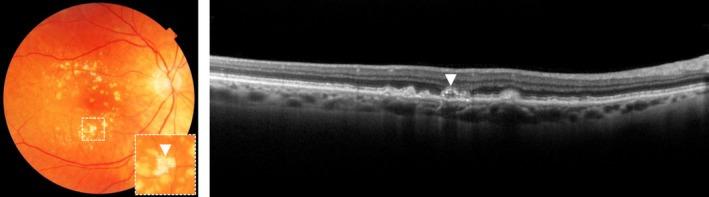

Age-related macular degeneration (AMD) is a degenerative disease of the macula, often leading to progressive vision loss. The rate of disease progression can vary among individuals and has been associated with multiple risk factors. In this review, we provide an overview of the current literature investigating phenotypic, demographic, environmental, genetic, and molecular risk factors, and propose the most consistently identified risk factors for disease progression in AMD based on these studies. Finally, we describe the potential use of these risk factors for personalised healthcare.

While phenotypic risk factors such as drusen and pigment abnormalities become more important to predict disease progression during the course of the disease, demographic, environmental, genetic and molecular risk factors are more valuable at earlier disease stages. Demographic and environmental risk factors such as age and smoking are consistently reported to be related to disease progression, while other factors such as sex, body mass index (BMI) and education are less often associated. Of all known AMD variants, variants that are most consistently reported with disease progression are rs10922109 and rs570618 in CFH, rs116503776 in C2/CFB/SKIV2L, rs3750846 in ARMS2/HTRA1 and rs2230199 in C3. However, it seems likely that other AMD variants also contribute to disease progression but to a lesser extent. Rare variants have probably a large effect on disease progression in highly affected families. Furthermore, current prediction models do not include molecular risk factors, while these factors can be measured accurately in the blood. Possible promising molecular risk factors are High-Density Lipoprotein Cholesterol (HDL-C), Docosahexaenoic acid (DHA), eicosapentaenoic acid (EPA), zeaxanthin and lutein.